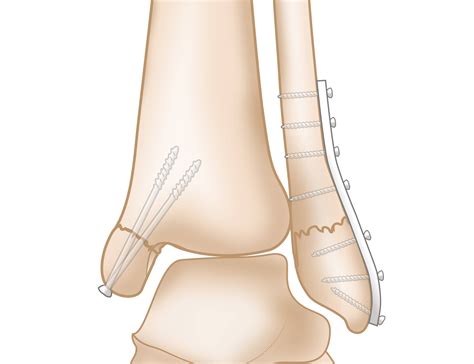

Surgical Treatment

Surgical treatment may be necessary for severe injuries, such as fractures or chronic instability. Surgical options may include:

• Open reduction and internal fixation (ORIF) for fractures

• Ligament repair or reconstruction for chronic instability

• Arthroscopy for minimally invasive procedures